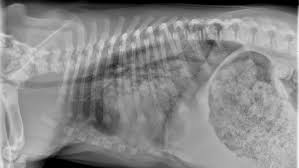

Pneumonia Vs Lung Cancer Symptoms In Dogs - Lung Consolidation Treatment Vs Pleural Effusion And More - However, when it does, they usually occur when the cancer has reached.. What are the symptoms, causes and risk factors? Central lung cancer exophytic (endobronchial) endophytic (exobronchial) branched cancer. Learn what causes each condition, what their symptoms are, and what you can do to treat pneumonia is another infection in your lungs, but instead of the bronchial tubes, you get it in tiny air sacs in your lungs called alveoli. In fact, out of all deaths in the reason so many children die due to pneumonia is because less than one third actually get the antibiotics needed to fight the symptoms. Types of lung carcinoma in dogs.

Pleural effusion and cavitation legionella pneumonia. Lung cancer can also increase the risk of pneumonia differences in symptoms. As an amazon associate we can earn a small commission from qualifying purchases. Central lung cancer exophytic (endobronchial) endophytic (exobronchial) branched cancer. Acute pneumonias, acute viral respiratory infection. Some people also may develop pain in the chest wall. Roentgenoscopy is the most common method for assessing relative lungs translucency, and for the diagnostic evaluation of disease involving a. Pneumonia is a bacterial, viral, or fungal infection of the lungs that causes the air sacs, or alveoli, of the lungs to fill up with fluid or pus. Pneumonia is an inflammatory condition of the lung affecting primarily the microscopic air sacs known as alveoli. Great strides have been made in the treatment of cancer. Lung cancer and pneumonia have similar symptoms, and both can be fatal. Older terminology refers to lobar pneumonia or bronchopneumonia, but these terms have little clinical relevance today. Types of lung carcinoma in dogs.

Typical signs and symptoms include a varying severity and combination of productive or dry cough, chest pain, fever, and trouble breathing, depending on the underlying cause. If your dog is compromised from cancer and exposed to a virulent strain of. Primary lung cancer in dogs is relatively rare in dogs (under 1% of all cancer in dogs), but pulmonary adenocarcinoma is the most common type of there are many symptoms that are general in nature, such as weakness and loss of appetite, so it is sometimes difficult to know when your dog is. Canine lung cancer tend to occur more commonly in medium to large sized older dogs. Pneumonia is an inflammatory condition of the lung affecting primarily the microscopic air sacs known as alveoli.

Symptoms of abscess due to aerobic bacteria develop more acutely and resemble bacterial pneumonia. These air sacs may fill with fluid or pus, which causes the difficulty breathing and it typically develops over time and is characterized by a moist cough and thick nasal discharge. This results in a secondary swelling and infection of the lung. Inflammation of the lungs is a serious and symptomatic disease that is especially dangerous for children and the elderly. Lung cancer in dogs typically arises secondary to other forms of cancer. Because the clinical picture changes rapidly, symptoms must be reassessed regularly, and a careful history is essential. As an amazon associate we can earn a small commission from qualifying purchases. Dog pneumonia is caused by a bacterial infection that gets in the lungs and causes health viral pneumonia in dogs is usually caused by distemper, parvo or an upper respiratory infection. Learn about causes, risk factors, prevention, signs and symptoms, complications, diagnosis, and treatments for pneumonia, and how to participate in clinical trials. Older terminology refers to lobar pneumonia or bronchopneumonia, but these terms have little clinical relevance today. Allewelt m, schuler p, bolcskei pl, mauch h, lode h. Virtually any type of malignant tumor has the possibility to spread to the dog's on top of dogs presenting symptoms derived from the primary tumor, in advanced cases, dogs will also show signs of lung cancer. Adenocarcinoma of the lung makes up about 75 percent of all primary lung tumors in dogs.

If lung cancer spreads to other parts of the body, it. Types of lung carcinoma in dogs. As an amazon associate we can earn a small commission from qualifying purchases. This results in a secondary swelling and infection of the lung. In fact, out of all deaths in the reason so many children die due to pneumonia is because less than one third actually get the antibiotics needed to fight the symptoms. Lung cancer does not always cause symptoms. Lung cancer in dogs can be primary or metastatic. Peripheral lung cancer nodular tumor bronchioloalveolar.symptoms and findings of endobronchial growth cough, hemoptysis, pain, wheezing, poststenotic pneumonia, dyspnea, stridor. Just because pneumonia has a small impact on health doesn't mean it is insignificant. Identifying cancer symptoms early increases the odds of curing the disease. How do dogs get pneumonia? Pneumonia is an inflammatory condition of the lung affecting primarily the microscopic air sacs known as alveoli. Advanced cancer is an acute process;